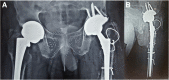

Radiographs at 6 weeks following surgery, showing trochanteric and femoral wiring for extended trochanteric osteotomy, and the revised stem and cup on the left hip. a Anteroposterior view. b Lateral view